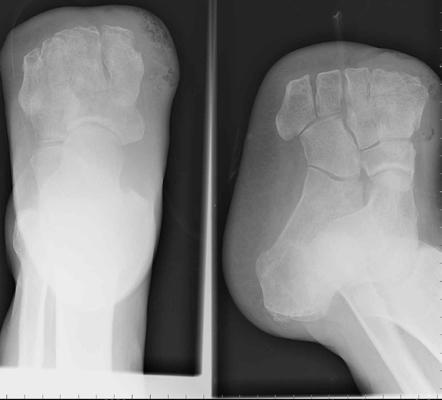

Amputations proximal to the transmetatarsal level often result in considerable gait

problems during walking. This is secondary to the loss of support and push-off.

When performed (often for the diabetic patient and in certain traumas), recent

improvements in preoperative testing (e.g. ultrasound) allow for a relative high accuracy

in predicting which patients will heal. The principle complication of the Lisfranc

amputation is a tendency towards an equinus deformity from the loss of dorsiflexor

attachments. If severe, such a deformity may require repeat amputation at a higher

level.